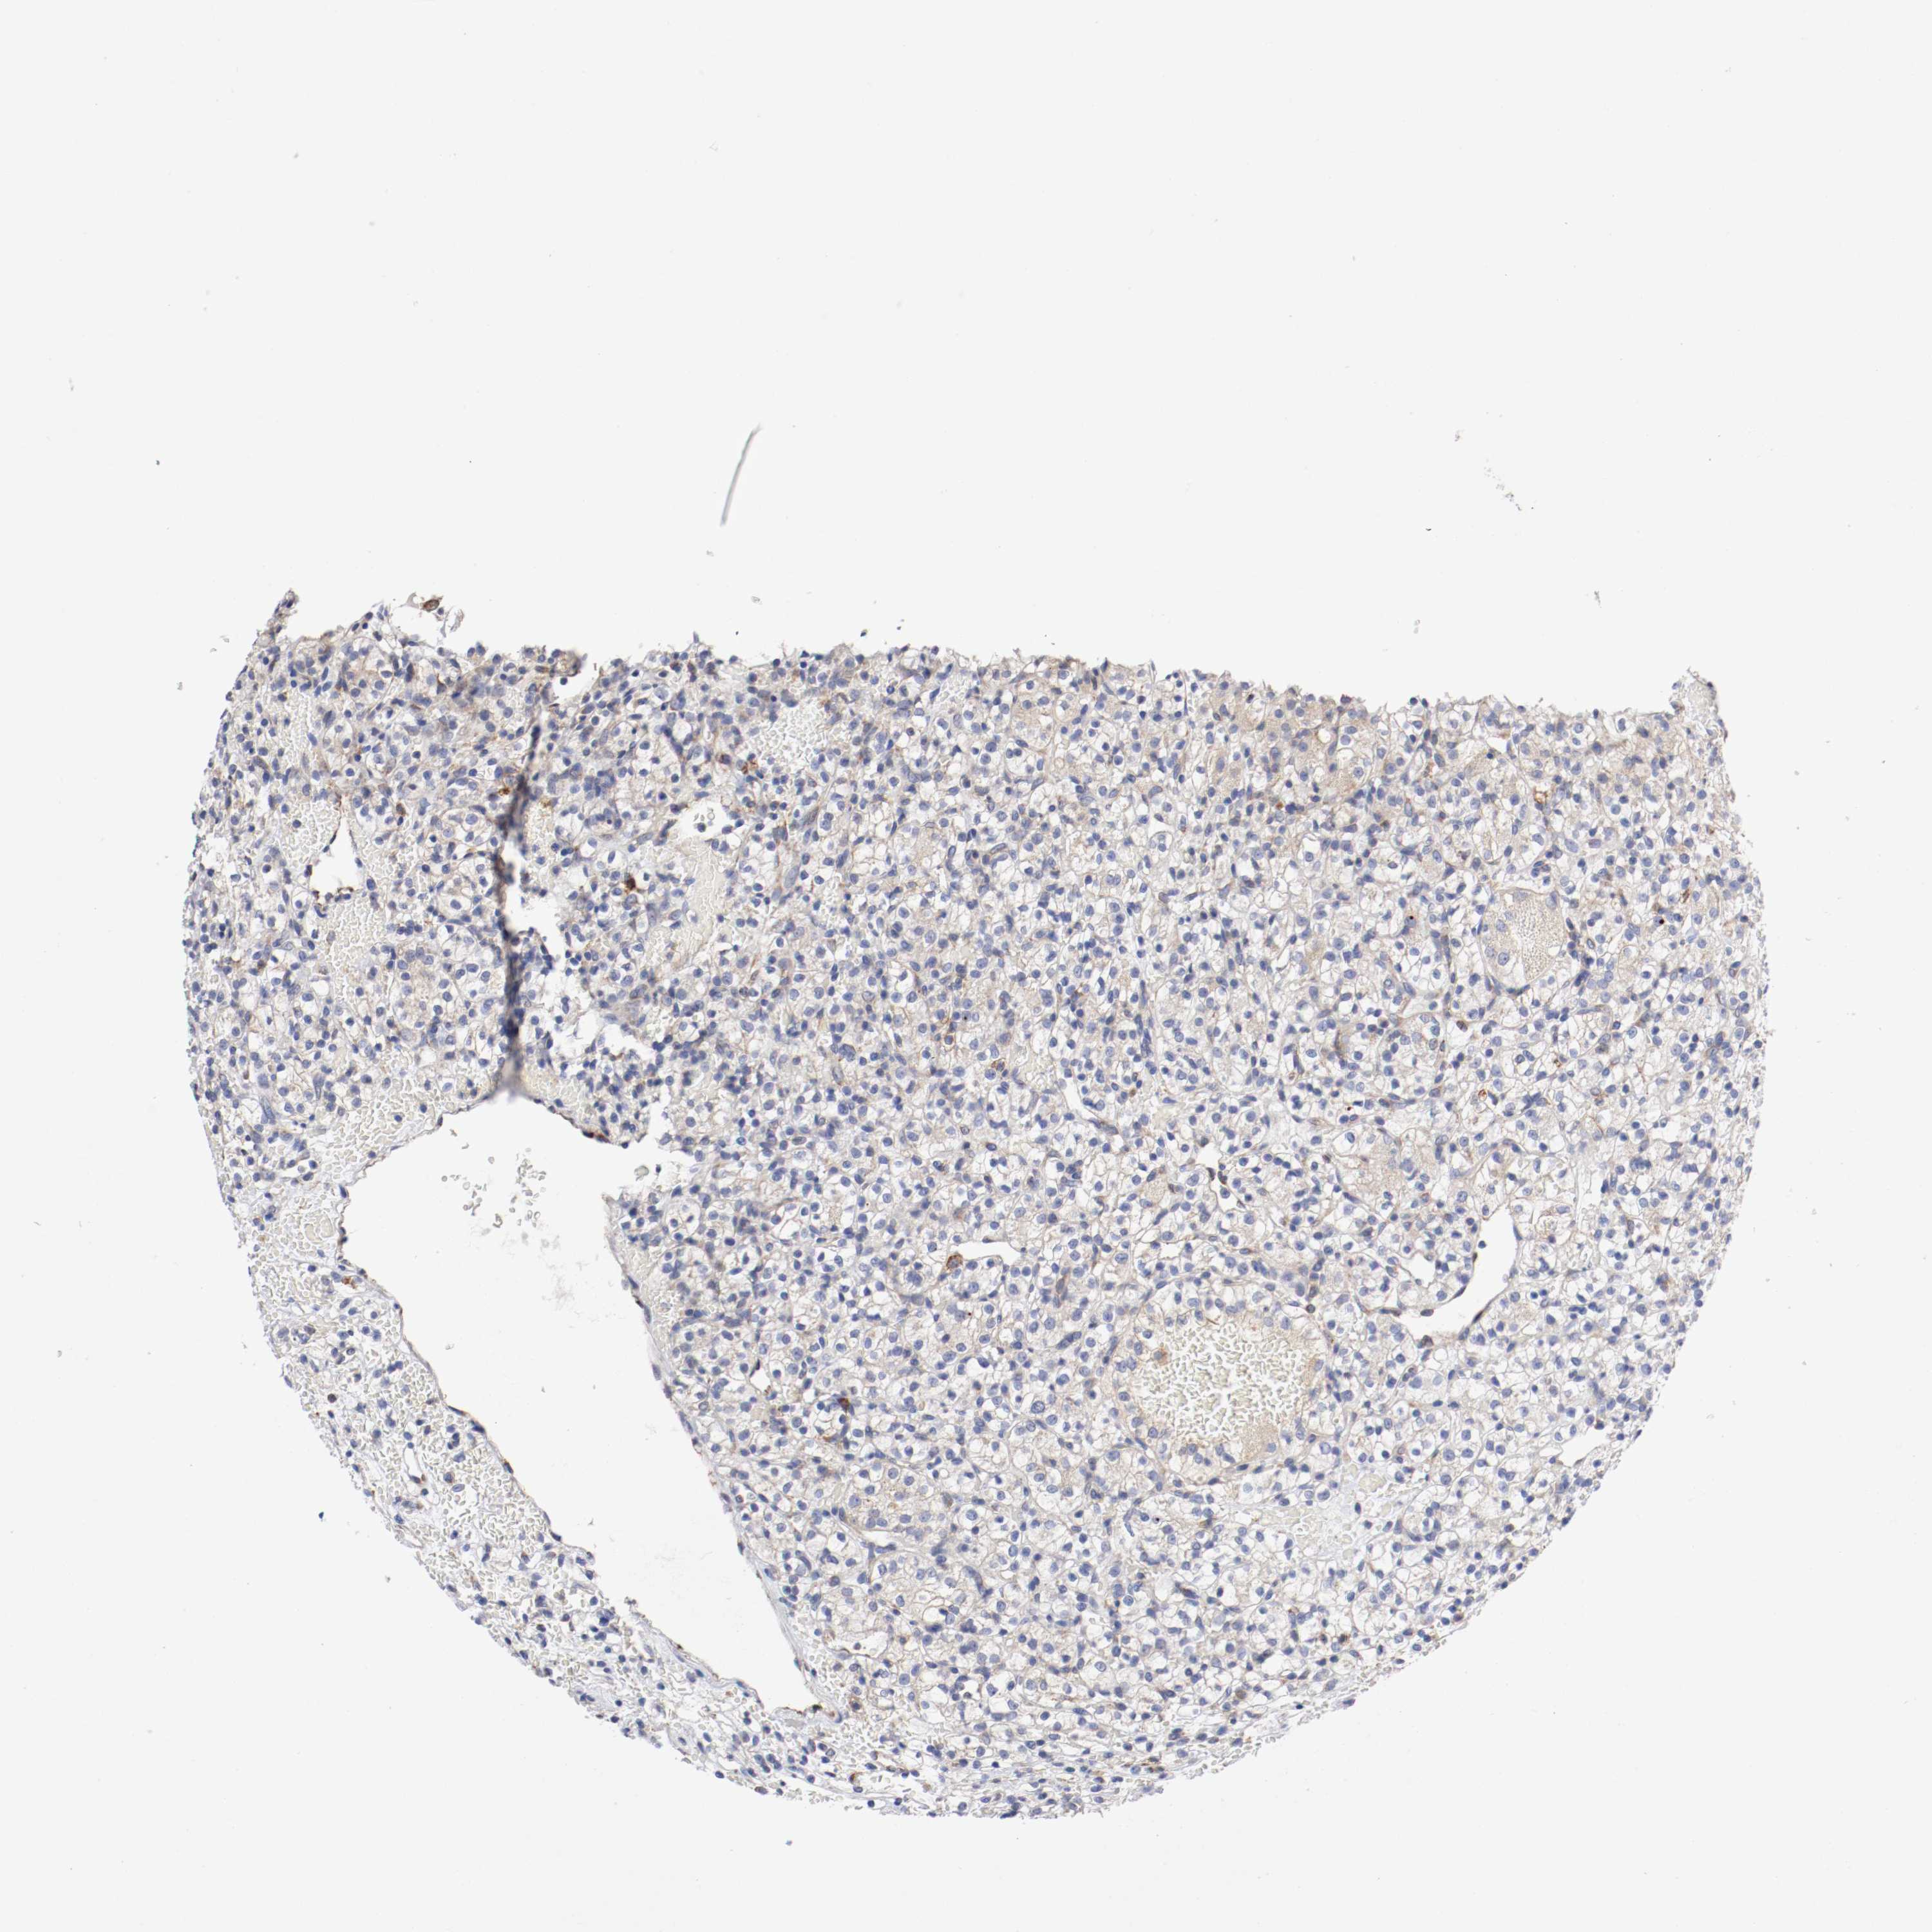

Renal cancer

Kidney chromophobe

KIDNEY CHROMOPHOBE (TCGA) - Interactive survival scatter ploti

TRAF2 is not prognostic in Kidney Chromophobe (TCGA)